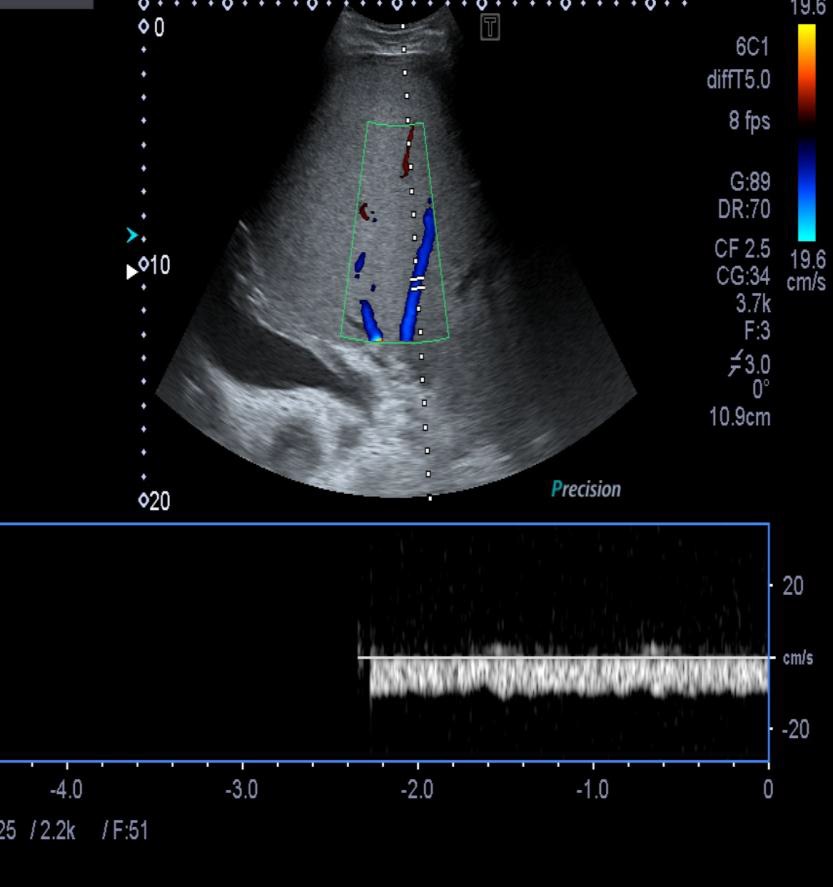

当怀疑BCS的时候,DUS应该被认为是首选的检查方式,其敏感性为87.5%【2】。正常肝脏所有三支肝静脉都能发现。正常情况下左和中肝静脉联合独立于右肝静脉引流到下腔静脉。超声检查之后,CT的应用可以确定BCS的诊断。CT可以证实造影剂通过肝静脉失败。由于不均匀灌注,肝脏实质表现为“斑驳(mottled)”或“跳骚咬的(flea bitten)”。门静脉高压的肝外特征如脾大和腹水也可被CT所发现。但是CT可以表现为假阳性[3],而DUS发现可以是有益的。MRI的优点与CT类似,而且还可以用于发现肾脏的受累。直接静脉造影已经罕见用于直接诊断,除非需要介入治疗。

诊断的敏感性85%,特异性90%

-

首选影像诊断技术

肝静脉,不可见

肝静脉缺乏血流

狭窄

肝静脉血栓

肝内侧支循环形成

肝段下腔静脉阻塞

肝尾叶肥大